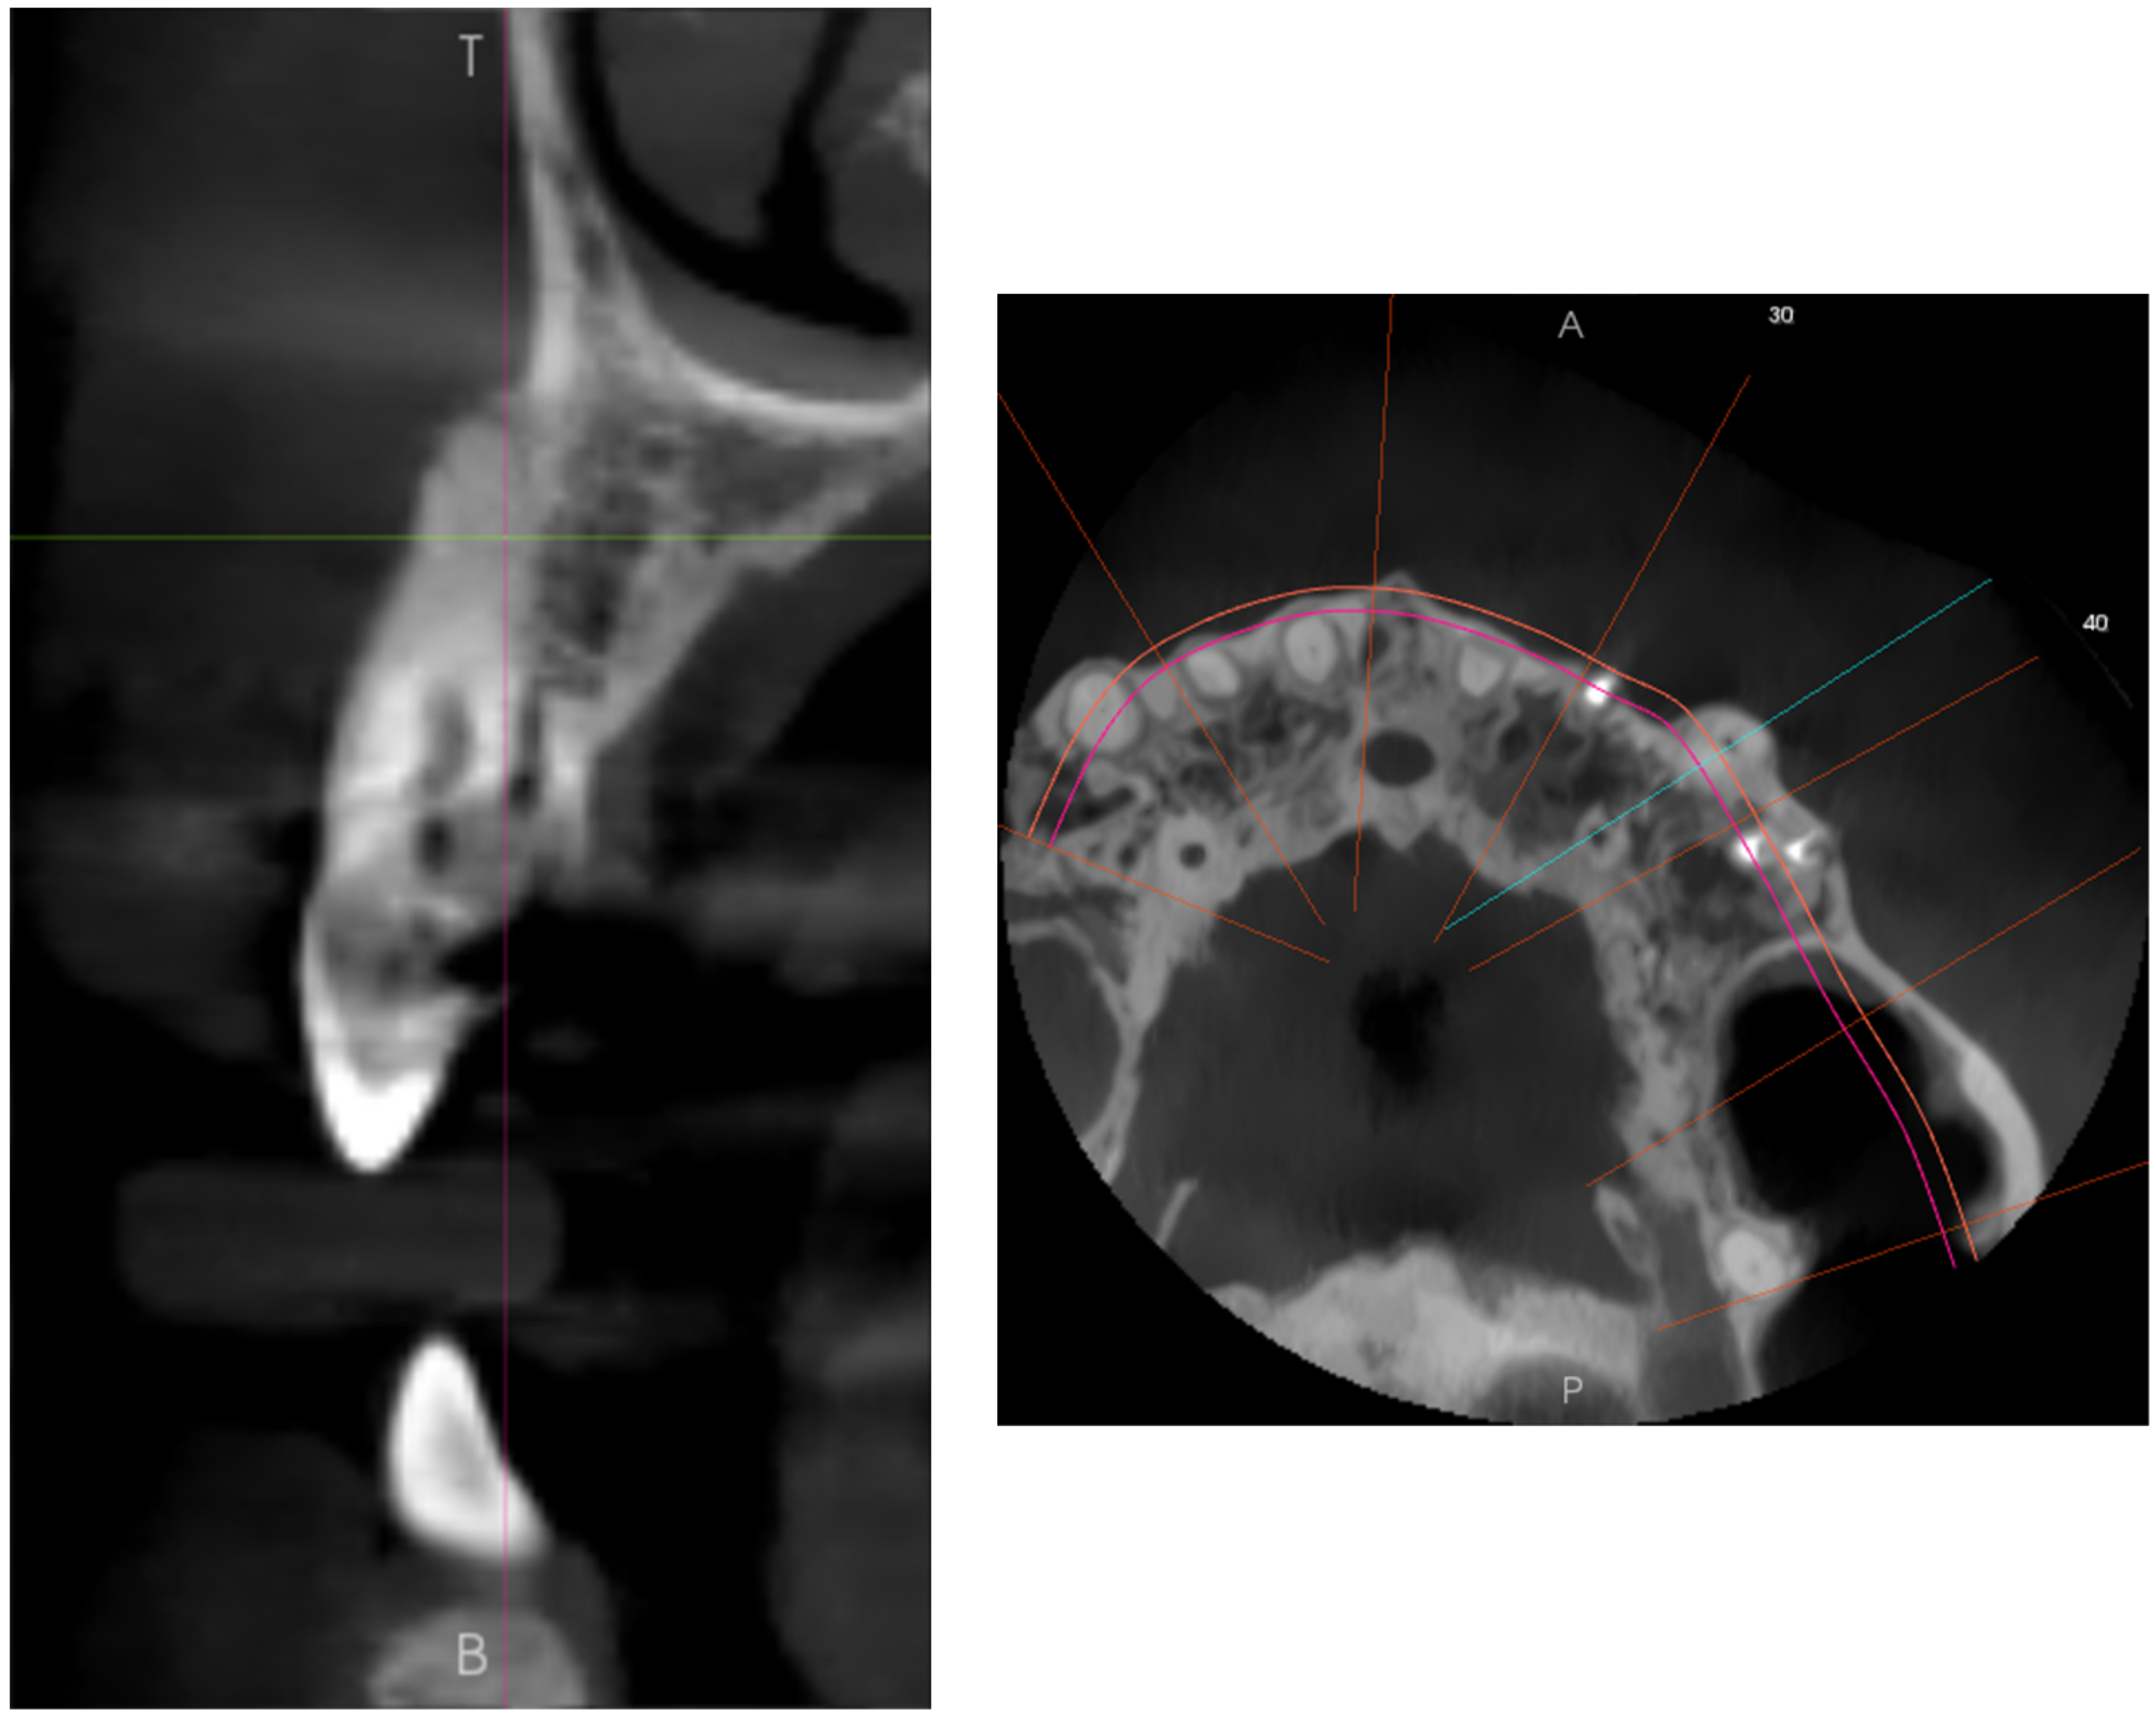

2.1. Report A

2.2. Report B

2.3. Report C

2.4. Report D